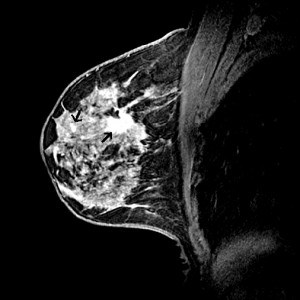

La MRI puede usarse con la mamografía con fines de detección en las mujeres con un alto riesgo de cáncer de seno, o puede usarse para examinar mejor las áreas sospechosas que se encuentran mediante una mamografía. Además, la MRI a veces se usa en las mujeres que han sido diagnosticadas con cáncer de seno para determinar mejor el tamaño real del cáncer y para buscar cualquier otro cáncer en el seno. este estudio resulta muy útil, si ya ha sido diagnosticada, para la planificación de la cirugía . En alguien que se sabe tiene cáncer de seno, algunas veces resulta útil examinar el seno opuesto con el fin de asegurarse de que no tiene ningún tumor. es muy común que las mujeres superen y extraigan tumores o cáncer de un seno, sin sospechar que en su otro seno también existe cáncer de mama el cual da síntomas después… con la resonancia magnética, se estudian ambos senos y se descarta esa posibilidad antes de la operación.

La resonancia magnética de mama es un examen médico no invasivo el cual diagnostica con mucha más certeza y eficacia las mamas. Emplea un campo magnético potente, para crear imágenes detalladas de los tejidos blandos, De esta forma, las imágenes pueden analizarse con una calidad de imagen y de contraste excepcional en high definition.

La RM de mama proporciona información valiosa acerca de muchas patologías mamarias que no pueden obtenerse fácilmente en otros estudios. Sin embargo la RM de mama no reemplaza a la mamografía o al ultrasonido, sino que es una herramienta suplementaria en casos como:

- Luego de ser diagnosticada con cáncer de mama se puede realizar una RMN del seno para determinar:Cuán grande es el cáncer y si involucra el músculo subyacente. Si hay otros cánceres en el mismo seno y si existe un cáncer insospechado en el seno opuesto. Si existe algún ganglio linfático anormalmente largo en la axila que podría indicar que el cáncer se ha desparramado hacia este sitio.